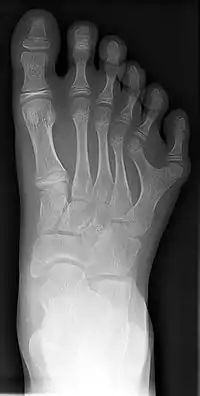

A polidactilia ou polidatilia (do grego πολύς, "muitos" e δάκτυλος "dedo") é uma anomalia causada pela manifestação de um alelo autossômico variável,dominante com expressividade consistindo na alteração quantitativa anormal dos dedos da mão (quirodáctilos) ou dos dedos do pé (pododáctilos).

Há uma variação muito grande na expressão dessa característica, desde a presença de um dedo extra, completamente desenvolvido, até a de uma simples profusão carnosa.

Ocorre do lado cubital (ulnar) da mão ou do lado peroneal (lateral) do pé. É a que tem herança autossômica dominante com penetrância incompleta, porém alta, e é cerca de 10 vezes mais frequente em negros do que em caucasoides.

Ocorre do lado radial da mão ou tibial (medial) do pé. Compreende vários tipos de defeitos (polidactilia do polegar, polidactilia do dedo indicador, polissindactilia, etc).